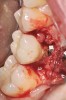

Fig 13. Radiograph depicting peri-implantitis.

Figure 13

Fig 14. Clear resin cement left on the implant abutment.

Figure 14

Fig 15. Implant abutment following cement removal.

Figure 15

If all implant-supported crowns could be designed for screw retention, no discussion of excess cement would be necessary. However, screw retention is not always possible depending on the location of the access opening and because of the unesthetic appearance in anterior restorations or the mesial/distal angulation of the implant compromising the path of insertion (Figure 12). Residual cement left after crown cementation on implants can lead to peri-implant inflammation, peri-implantitis, and eventual loss of the implant (Figure 13 through Figure 15).25 The presence of lingering excess cement can encourage the development of bacterial colonization and peri-implantitis. Conversely, when too little cement is used, voids in the cement layer can occur and the prosthesis can become loose.26 The deeper the implant crown margin, the more difficult it is to remove excess cement.27

Radiopaque cements that contain zinc phosphate and zinc oxide (with and without eugenol) should be considered to help identify excess interproximal cement; however, this should be used secondarily to proper margin height and careful removal of cement during cementation. Resin cements lack the same opacity as zinc-containing cements and have been shown to be the most difficult to remove.28 Often in the process of removing this excess cement, the abutment surface becomes scratched and damaged, potentiating further plaque accumulation.29

Several modifications in abutment design and cementation have been suggested. Placing vent holes in the abutment during fabrication or leaving most of the screw-access chamber open for access has reduced the amount of cement that expresses out into the sulcus.26 It is also beneficial to extraorally express excess cement on an abutment replica prior to final crown seating to minimize complications. If retrievability is desired with cementable implant crowns, weaker cements (eg, zinc oxide eugenol) should be used first and progressively changed until the desired retention is achieved.